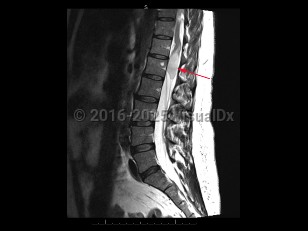

Cauda equina syndrome is a neurologic emergency where damage to the lumbosacral plexus leads to loss of lower motor neuron function. Trauma, tumors or abscesses, large lumbar disk herniation, and spinal stenosis are some of the etiologies of this condition.

Onset is typically gradual but can be acute. Signs and symptoms include severe back pain that may radiate into one or both legs, saddle anesthesia, leg weakness or paraplegia, urinary or bowel dysfunction, sexual dysfunction, and gait disturbance. There may be reduced or absent patellar, Achilles, anal, and bulbocavernosus reflexes.